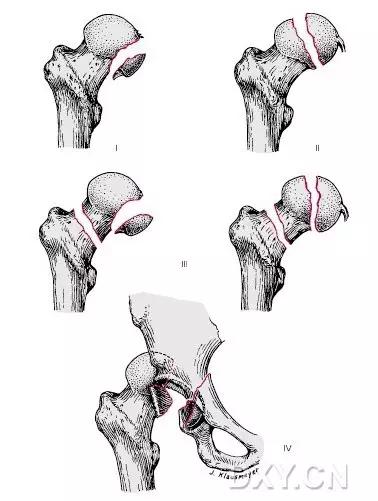

6. Pipkin 骨折

股骨头骨折。1957 年,Pipkin G 在文献中对其进行详细的描述并分型,至今仍在很多文献中被采用。

-

Ⅰ型:骨折块在圆韧带的下方;

Ⅱ型:骨折块在圆韧带的上方;

Ⅲ型:Ⅰ、Ⅱ两型任意一种伴股骨颈骨折;

Ⅳ型:Ⅰ、Ⅱ两型任意一种伴髋臼骨折 。